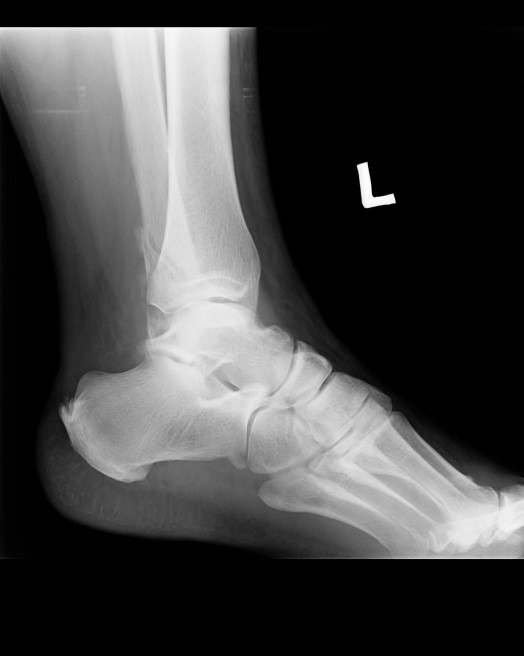

Na rentgenogramie przedstawione jest złamanie Saltera-Harrisa typu

Ilustracja do pytania 19

A. II odcinka bliższego kości piszczelowej.

B. V czwartej kości śródręcza.

C. I ześlizgnięcie bliższej nasady kości udowej lewej.

D. III nasady dalszej kości piszczelowej.